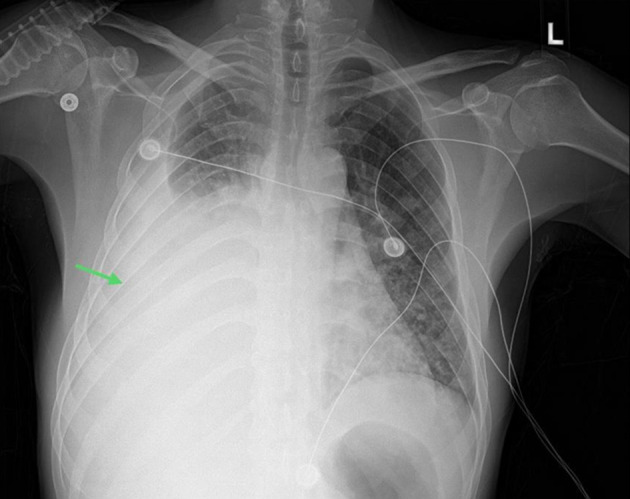

卡波西肉瘤(KS)是一种影响皮肤和淋巴结的血管增生性肿瘤。人类疱疹病毒-8(HHV-8)会感染血管内皮,并通过产生血管内皮生长因子和细胞因子诱导血管生成,从而引发 KS。KS 的特征是皮肤和粘膜出现紫斑或色素沉着斑,内脏受累非常罕见。肺部 KS(PKS)是一种极为罕见的 KS 内脏表现,预后较差。PKS 常表现为咳嗽、咯血、胸膜炎性胸痛、发热和体重减轻。在本系列病例中,我们分享了诊断和治疗两名 PKS 患者的经验。我们还简要回顾了这种罕见疾病的流行病学、症状和体征、诊断和治疗。

Kaposi sarcoma (KS) is an angioproliferative neoplasm that affects the skin and lymph nodes. Human herpesvirus-8 (HHV-8) triggers KS by infecting the endothelium and inducing angiogenesis through the production of vascular endothelial growth factors and cytokines. KS is characterized by purplish or hyperpigmented plaques involving the skin and mucous membranes, and visceral involvement is very rare. Pulmonary KS (PKS) is an exceedingly rare visceral manifestation of KS and has a poor prognosis. PKS often presents with cough, hemoptysis, pleuritic chest pain, fever, and weight loss. In this case series, we share our experience in diagnosing and treating two patients with PKS. We also provide a concise review of the epidemiology, signs and symptoms, diagnosis, and management of this rare condition.